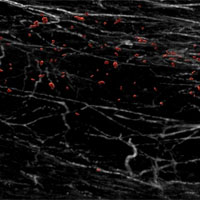

New way to infiltrate hard-to-treat cancers

Scientists have found a way to deactivate DDR1, a molecule that forms a barrier "like barbed wire" in tumours. By removing this barrier, anti-tumour immune cells could target aggressive forms of breast cancer.